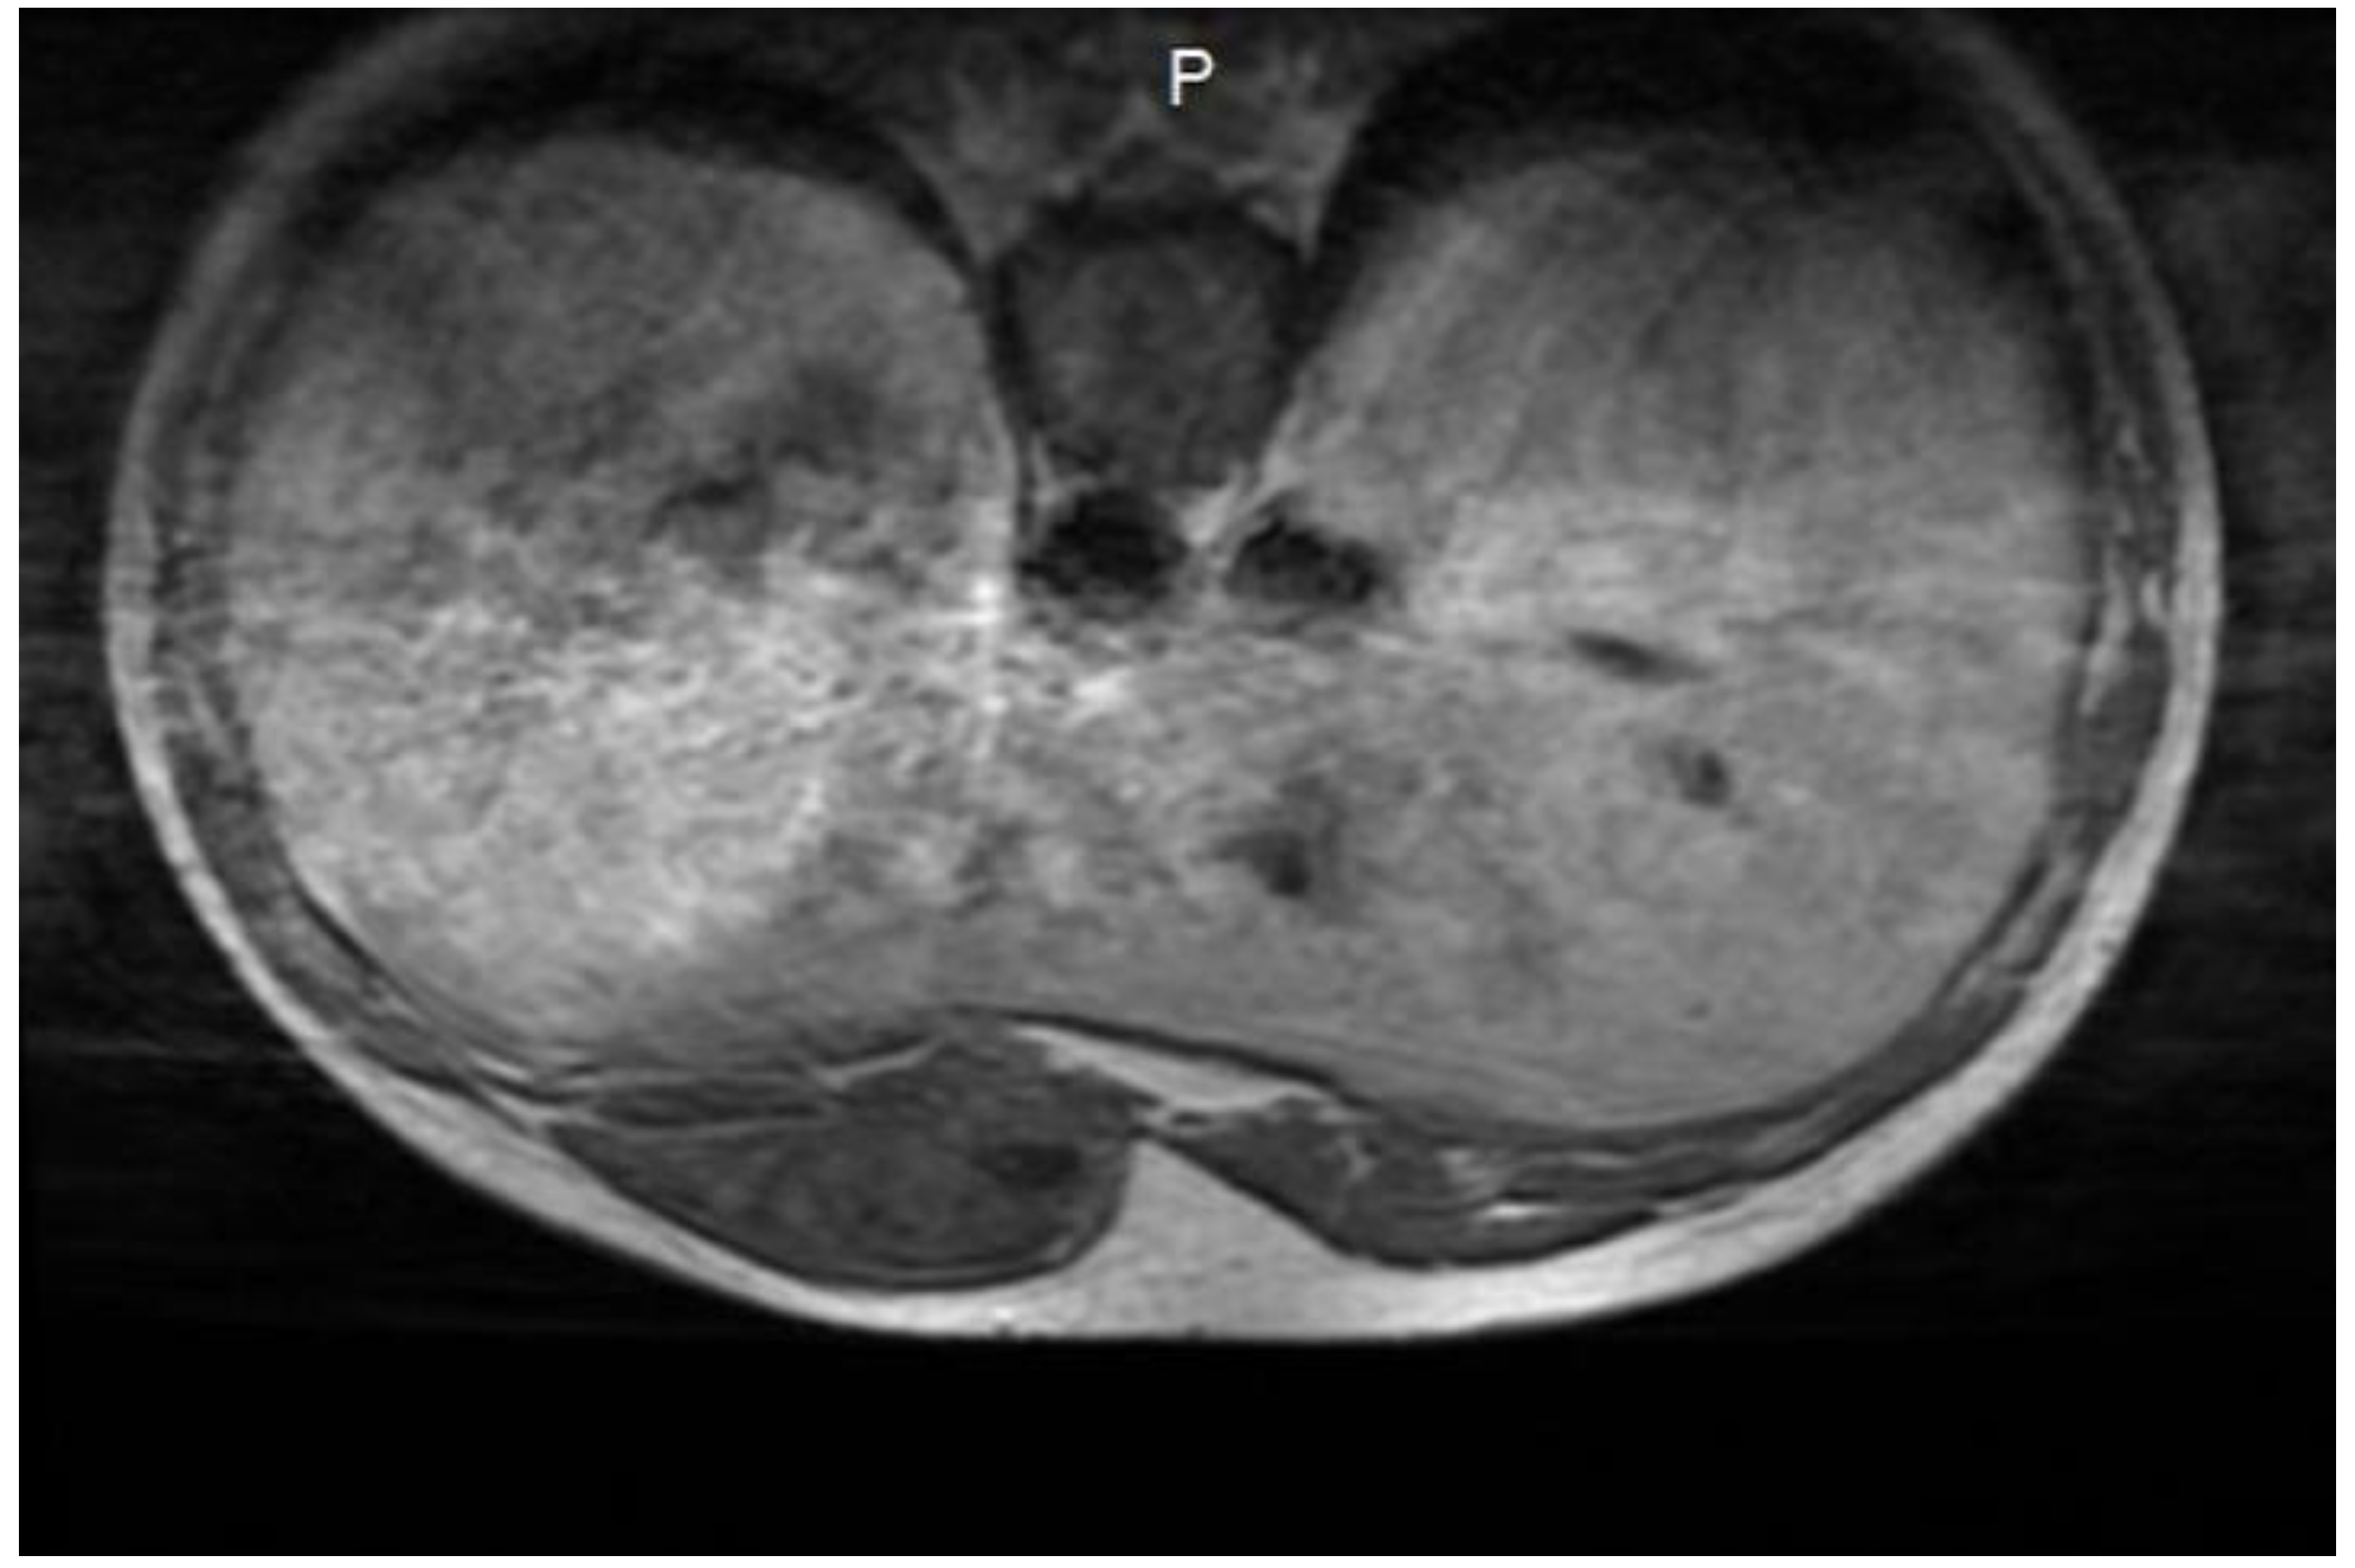

A soft-tissue ultrasound revealed a left paramedian parenchymatous mass measuring 4 × 2.7 cm, situated at the base of the hypochondrium, corresponding to the anterior XI-XII intercostal spaces. A contrast-enhanced thoraco-abdominal CT scan (Figure 1) further identified a well-defined, oval, intramuscular mass (22 × 48 × 55 mm, AP/LL/CC) within the proximal segment of the left rectus abdominis muscle, anterior to the VI-VII-VIII costal cartilages. There was no evidence of intra-abdominal or intrathoracic extension, adjacent tissue invasion, bone lysis, or suspicious adenopathies.

Figure 1. Thoraco-abdominal CT scan - desmoid tumor with intrathoracic localization.